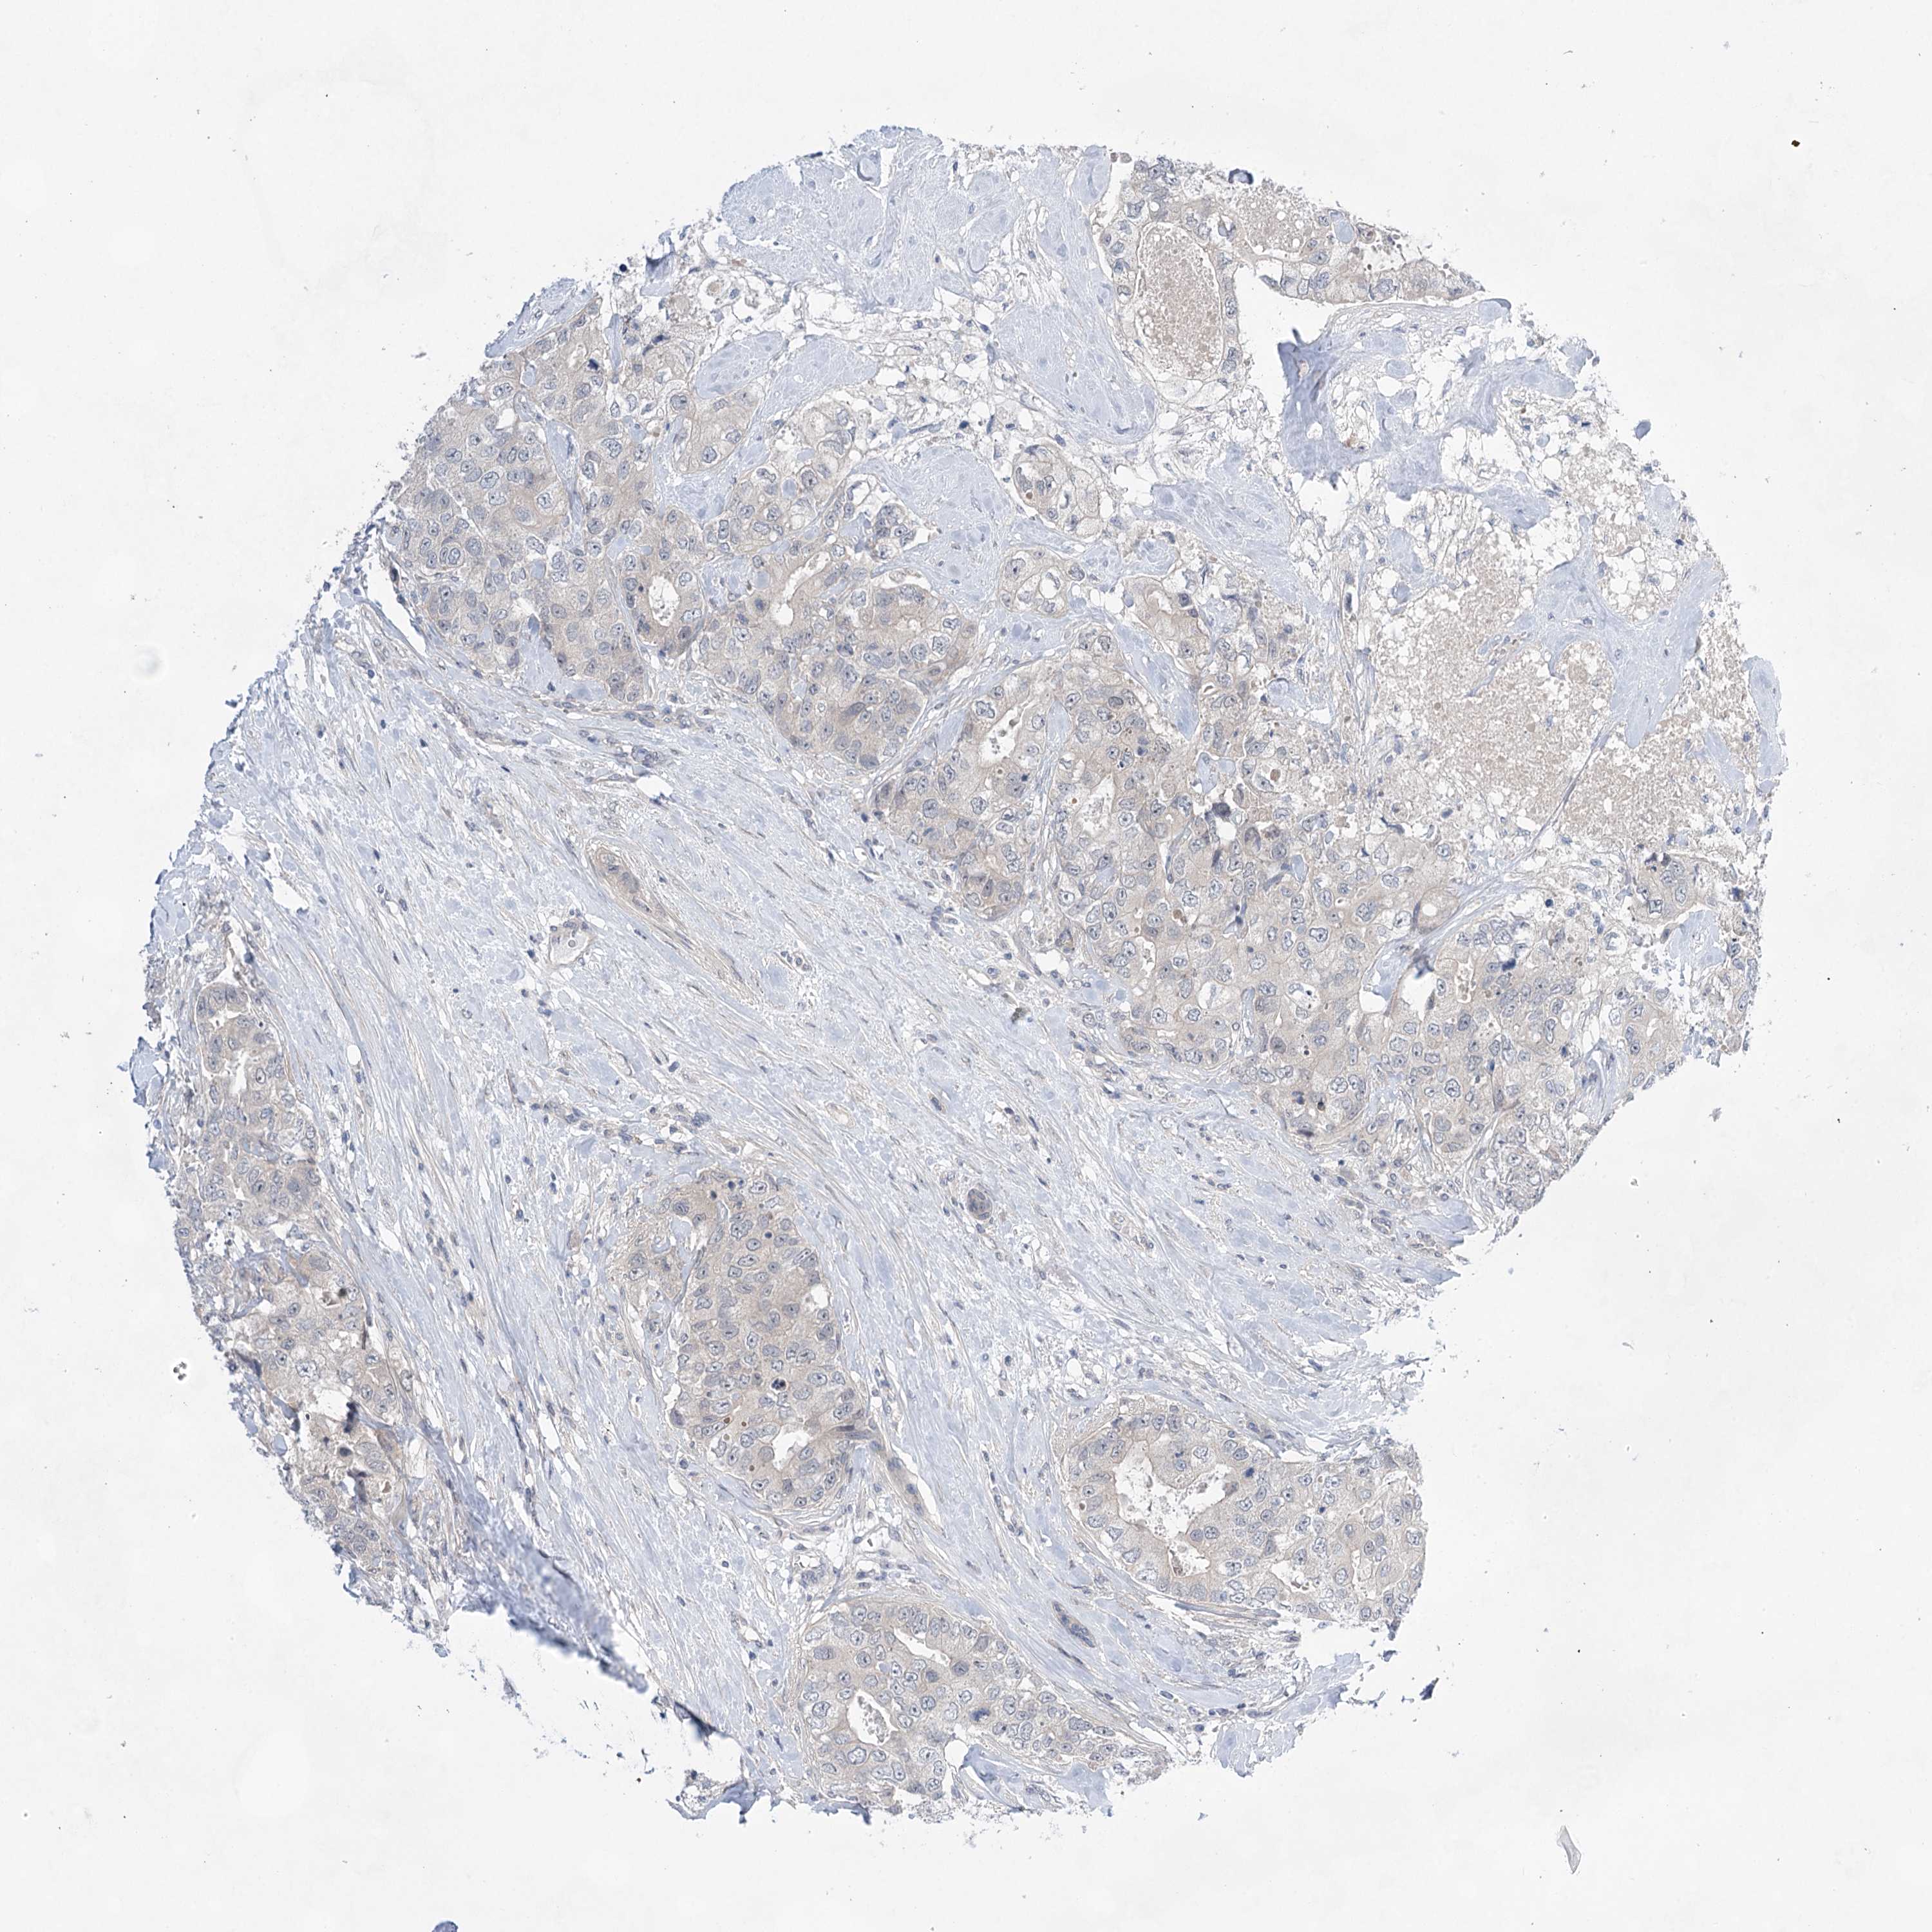

CANCER BREAST CANCER Show tissue menu

BRCA TCGA BRCA VALIDATION PROTEIN EXPRESSION

Breast cancer

Human cancer

LALBA is not prognostic in Breast Invasive Carcinoma (TCGA)